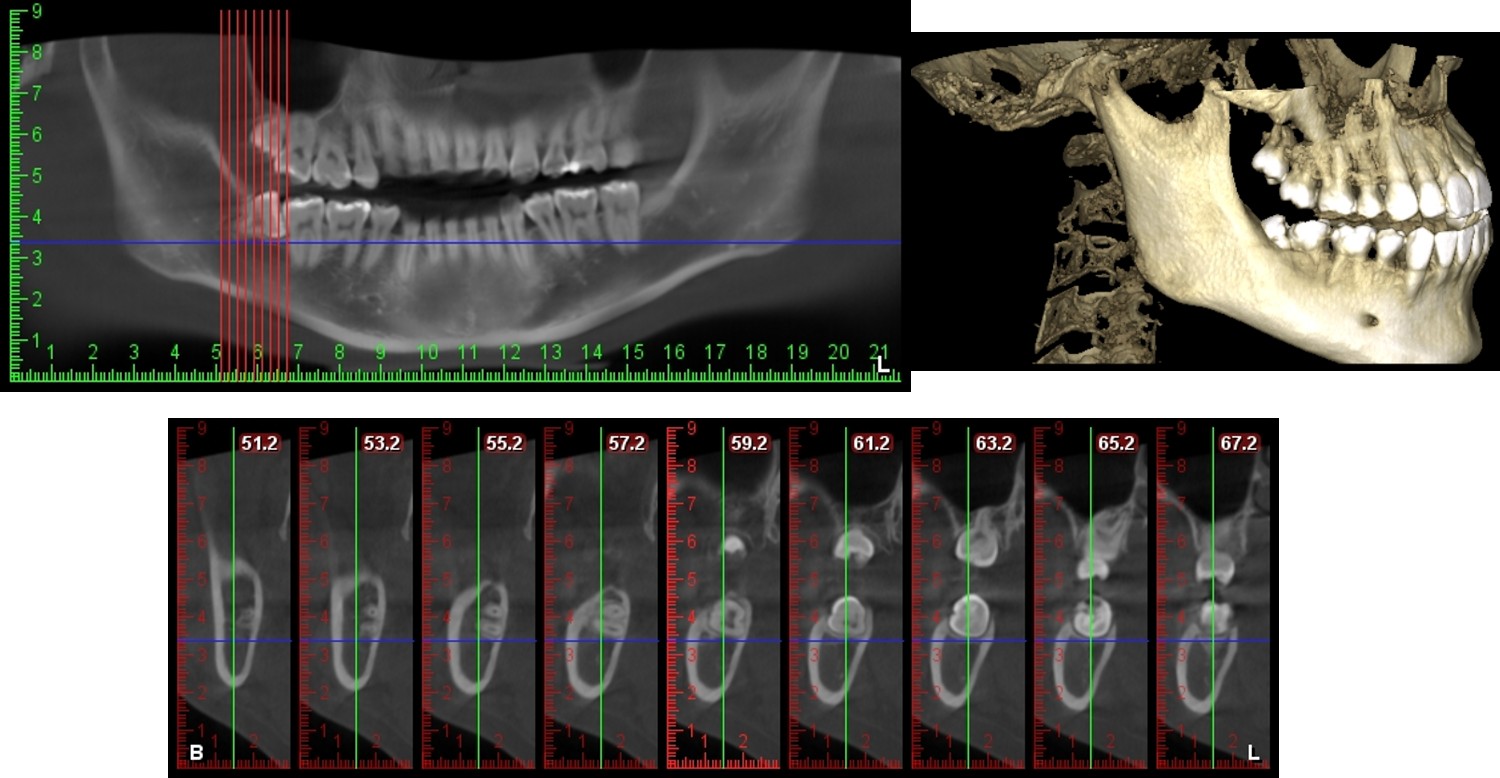

牙科專用的3D電腦斷層攝影;與傳統醫療電腦斷層相比較,輻射劑量只有一般電腦斷層的1/50;切片厚度一般醫療電腦斷層是2.0公厘,牙科3D電腦斷層則只有0.1公厘,就診當天馬上拍攝電腦斷層,馬上獲得立體影像。

電腦斷層顯示下齒槽神經距離遠